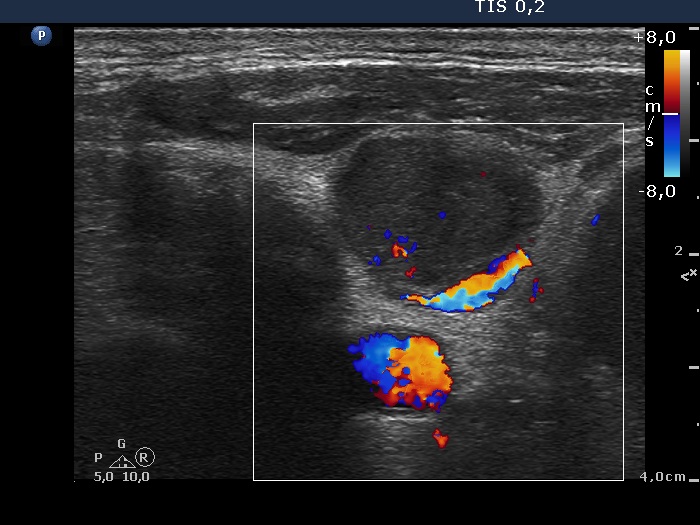

Thyroid cancers - case 1270 (ultrasonographic picture 12)

Left side of the neck, transverse scan, color Doppler mode. A large vessel can be seen at the dorsal border of the node.